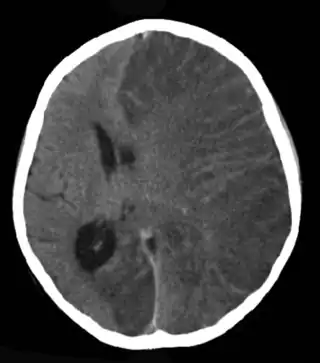

Escáner cerebral de una niña con encefalitis de Rasmussen.